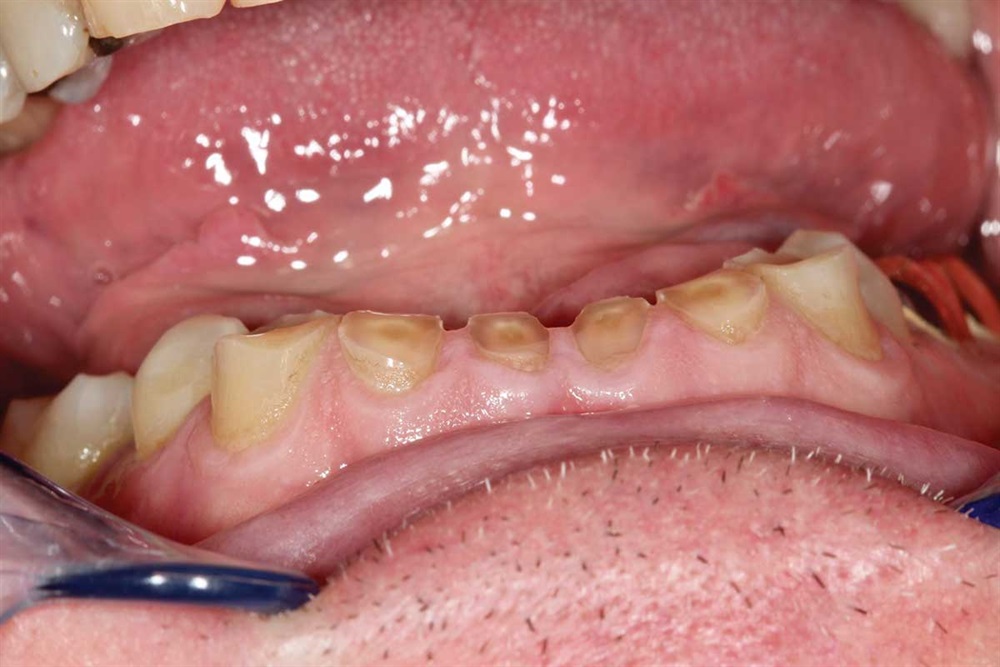

Fig. 7: Z250 A2 composite, AllBond 2 and Premier Dental Cure-Thru matrix bands were used.

Fig. 8: First tooth done, but not finished. I built up the incisors about 5mm.

Fig. 11: Got the teeth all hitting with the same pressure. However, I kept the lower central incisors in lighter occlusion because they were worn more than the rest.